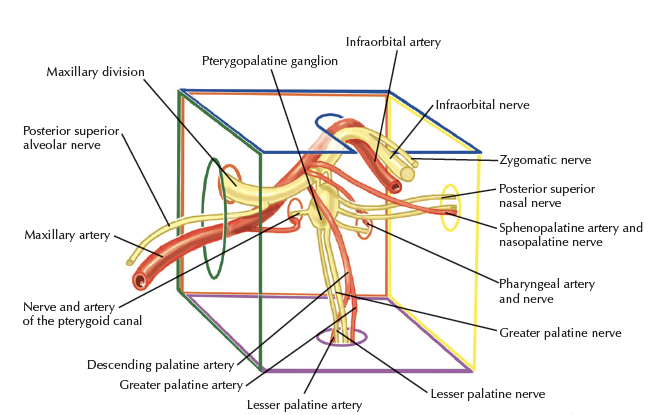

Maxillary a.

- Mandibular part

- Pterygoid part

- Pterygopalatine part

Info

Maxillary a.通過pterygoid muscle淺層,穿入pterygopalatine fossa

First part

- Ant. tympanic a.

- 進入 tympanic cavity,供應 tympanic membrane

- Middle meningeal

- 被Auriculotemporal n. 環繞

Second part

皆有(CN V3)伴行,除了Buccal n.為sensory,其為motor

- Ant./post. deep temporal a.

- Buccal a.

- Masseteric a.

- Pterygoid a.

Third part

皆有sensory 伴行,穿入pterygopalatine fossa

- Sphenopalatine a.

- 最終分支,進入 Sphenopalatine foramen,支配鼻竇

- Vidian a.

- Vidian n.

- maxillary tuberosity

- on alveolar bone

Pterygopalatine ganglion

Pterygopalatine Fossa

Pterygomaxillary fissure

Infratemporal fossa

- PSA n.

- Maxillary a.

- Variable network of veins into the pterygoid plexus

Pterygopalatine ganglion

- Greater/lesser palatine n.

- Nasopalatine n.

- Post. sup. nasal n.

- Pharyngeal n.